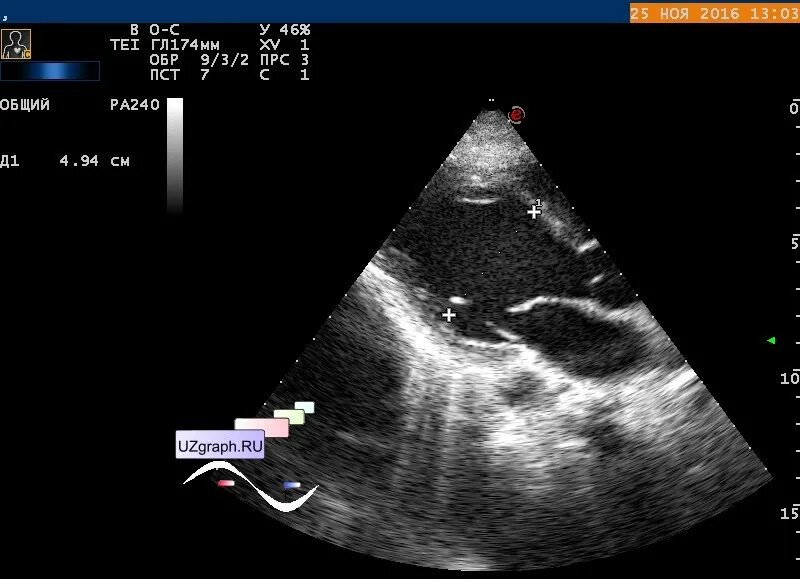

Узи сердца. ультразвуковое исследование сердца. узи сердца исследование. патологии сердца на узи.

Узи сердца. эхограмма сердца. ультразвуковое исследование сердца.

Ультразвуковое исследование сердца - эхокг что это. эхокардиография (узи сердца эхо кг). узи сердца норма снимок. эхокардиография норма и патология.